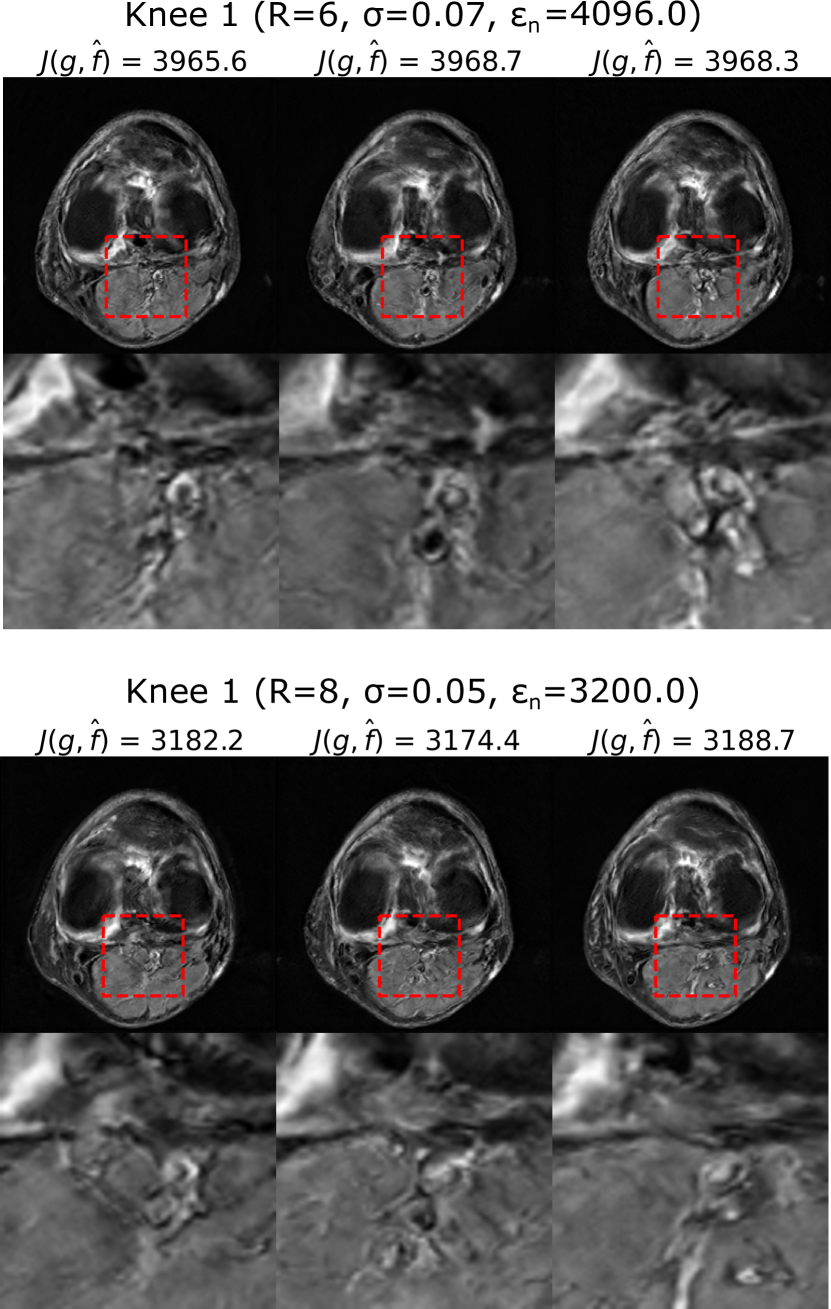

Figure 5 shows samples of data-consistent alternate solutions obtained with PULSE++ from k-space produced by Knee 1 when the sampling pattern or the noise level is varied, e.g. with sampling conditions {R=6𝑅6R=6, σ=0.07𝜎0.07\sigma=0.07} and {R=8𝑅8R=8, σ=0.05𝜎0.05\sigma=0.05}. The corresponding PULSE++ parameters were {γ=104𝛾superscript104\gamma=10^{-4}, λc=0.01subscript𝜆𝑐0.01\lambda_{c}=0.01} and {γ=105𝛾superscript105\gamma=10^{-5}, λc=0.001subscript𝜆𝑐0.001\lambda_{c}=0.001} respectively. Additionally, using the same pre-trained StyleGAN model, data-consistent alternate solutions were obtained with PULSE++ {γ=0.01𝛾0.01\gamma=0.01, λc=0.001subscript𝜆𝑐0.001\lambda_{c}=0.001} from k-space data with R=8𝑅8R=8 and σ=0.07𝜎0.07\sigma=0.07 corresponding to Knee 2 (Fig. 2), as shown in Fig. 6.

Refer to caption

Figure 5: Alternate data-consistent solutions obtained using PULSE++ from k-space data produced by Knee 1 for different sampling conditions {R=6𝑅6R=6, σ=0.07𝜎0.07\sigma=0.07} (top) and {R=8𝑅8R=8, σ=0.05𝜎0.05\sigma=0.05} (bottom) using the same MRI-StyleGAN model as in Fig. 4. Zoomed-in images of the same region in the alternate solutions indicated by a red bounding box show distinct structures. The alternate solutions are displayed in the grayscale range [0,1]01[0,1].